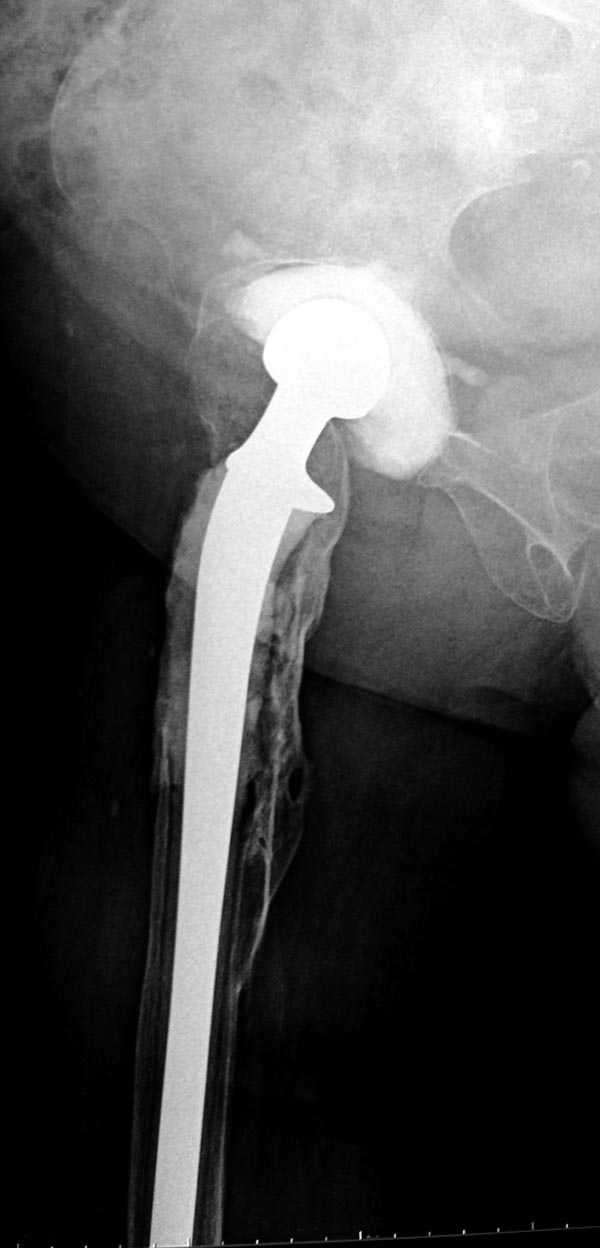

В дальнейшем заменил бы наружный фиксатор из частей аппарата Илизарова на более стабильный - стержневой фиксатор таз-бедро. В тазу можно применить полукольцо стержнями за крыло таза и дистально 2-3 стержня между передней и боковыми головками четерехглавой мышцы. Дельтовидная рама сверху вниз усилит конструкцию.

Можно на аппарате или на вытяжении немного дотянуть для создания запаса длины.

Следующий этап восстановление применением Blade Plate. Универсальный имплант и сегодня является уникальным по механическим характеристикам для восстановления проксимального отдела бедра где имеется сложная биомеханика.

Имеющиеся 130 градусные для вальгуса пластины от

Synthes короткие всего на две дырки, выход, обычная длинная 95 градусная Blade Plate разгибается до 105-110 градусов. Металл трудно поддается деформации, и его не согнуть между тепловой батереей в операционной, надо подготовить заранее после предварительного нагрева в механической мастерской.

Проведя клинок горизонтально в шейку, и соединив с

диафизом бедра создаем небольшой вальгус, тем самым увеличиваем длину конечности. Образовавшийся дефект кости надо заполнить блоком цемента, который предупреждает инфицирования и дает устойчивость конструкции. После затихания процесса можно приступить ко вторичному заполнению аутокостью или можно применить костную массу из того же местного костного регенерата.